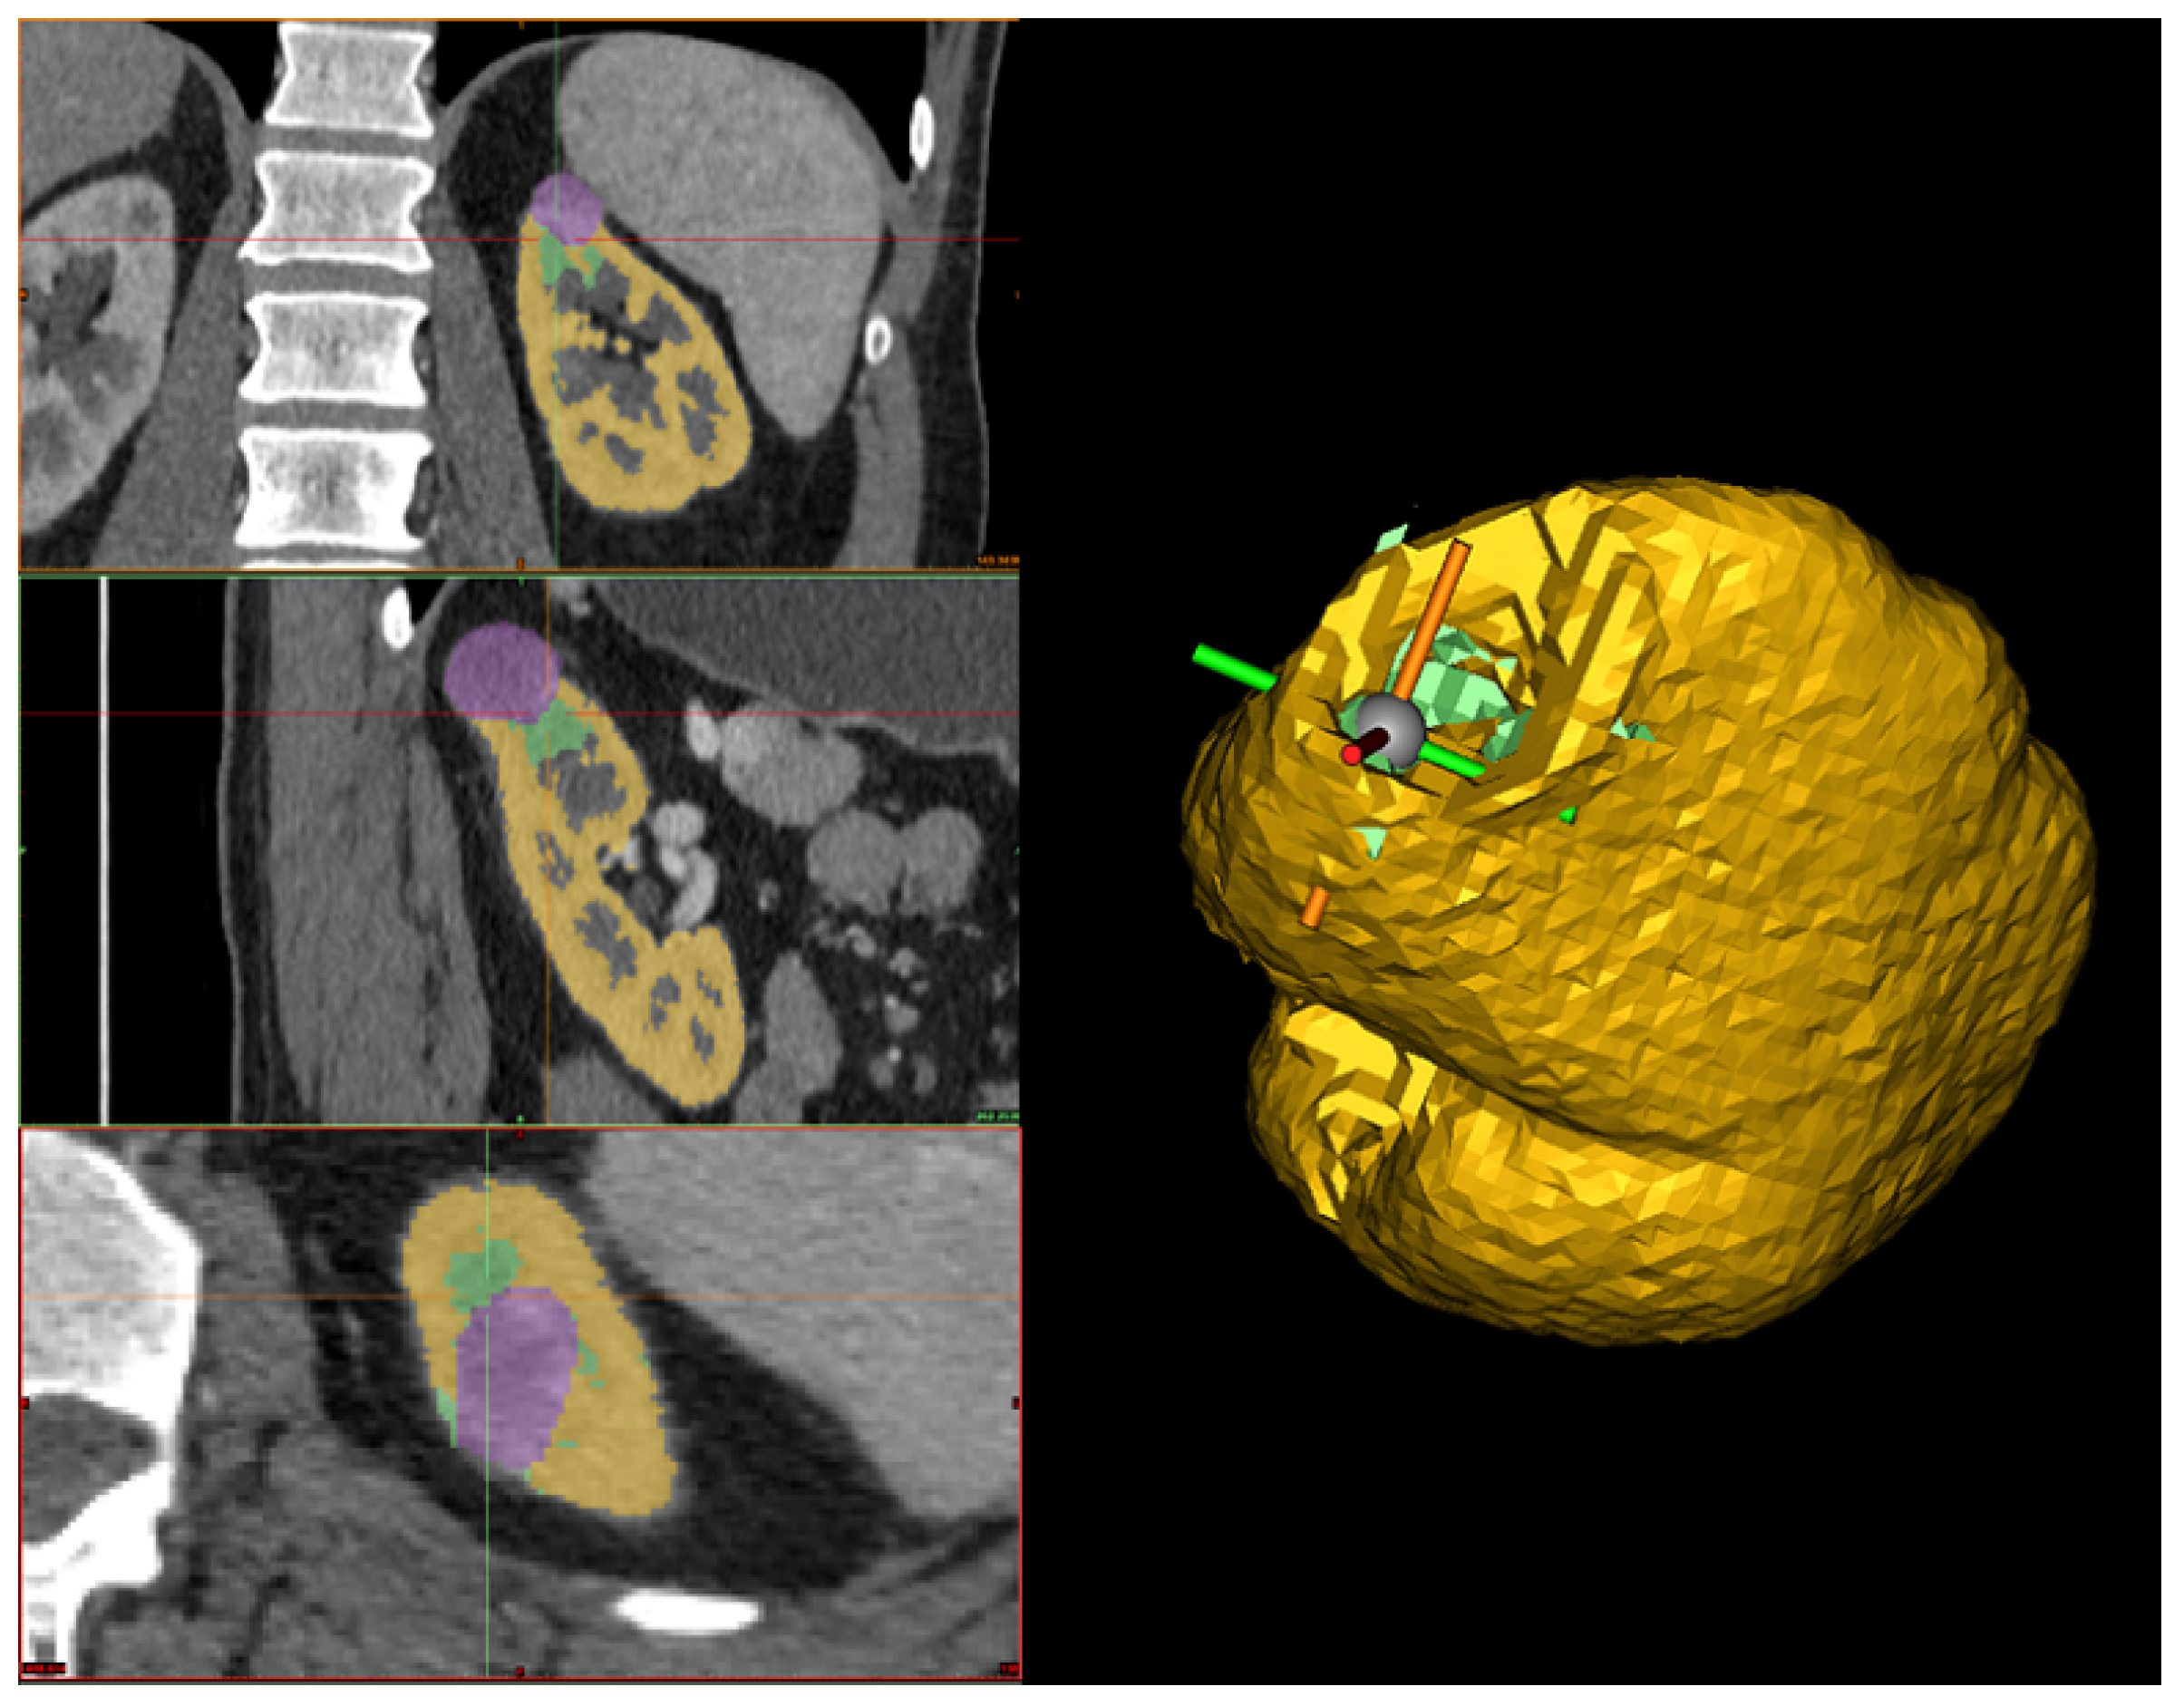

Tumor segmentation. In this stage, similar to kidney segmentation, a hybrid approach is employed, which encompasses semi-automatic processes executed through software tools and manual interventions performed by a human operator. Nevertheless, the segmentation process for tumors differs from that of kidneys. In this case, the tumor contour is directly outlined. Initially, the human operator must identify the tumor in all three sections (i.e., axial, coronal, and sagittal) from the CT scan. Subsequently, the tumor’s boundary must be outlined on each section using the 3D interpolate tool available in Materialise Mimics Inprint. Specifically, when delineating the tumor’s boundary, Materialize uses an algorithm that semi-automatically segments the tumor over the various slices and produces a 3D reconstruction of it, which may change depending on the selection of the tumor boundary in the next slice (see Figure 4).

Figure 4. On the left-hand side, the automated 3D interpolation of the tumor is shown based on the manually drawn silhouette in the three planes, where the green region represents the tumor in each plane. On the right-hand side is the 3D reconstruction of the tumor obtained from the interpolation of the three axes.